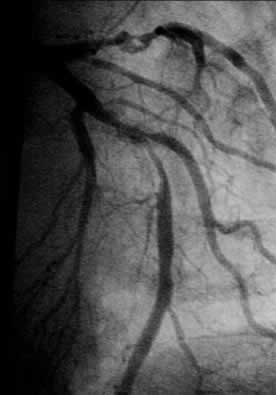

| Diagnosis: OMI, AP, DVD Present Illness: '01.1.25 AMI '01.8.23 POBA for #13 '01.10.1 AMI, POBA for #2 |

| Final CAG Findings:'01.10.1 CAG&PCI: POBA for #2 #7 90% (severe calcified) |

LAD: 2.15mm Diagonal: 1.75mm |

KBT LAD: 3.5mm Diagonal: 2.5mm |